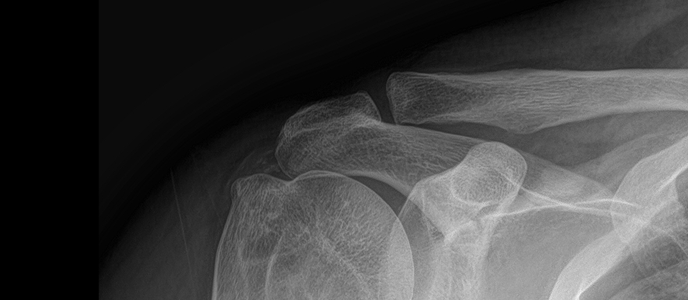

치료 증상 잘 때도 아파서 깸 , 팔 들기 힘듦

나이/성별 50세 / 여성

치료 내용 석회쇄석흡인술 후 호전

치료 기간 2025-02-22 ~ 2025-02-22

※ 해당 사진은 수정없는 실제 치료사진입니다. 환자의 치료결과는 환자의 상태, 치료방법 등에 따라 차이가 발생할 수 있습니다.